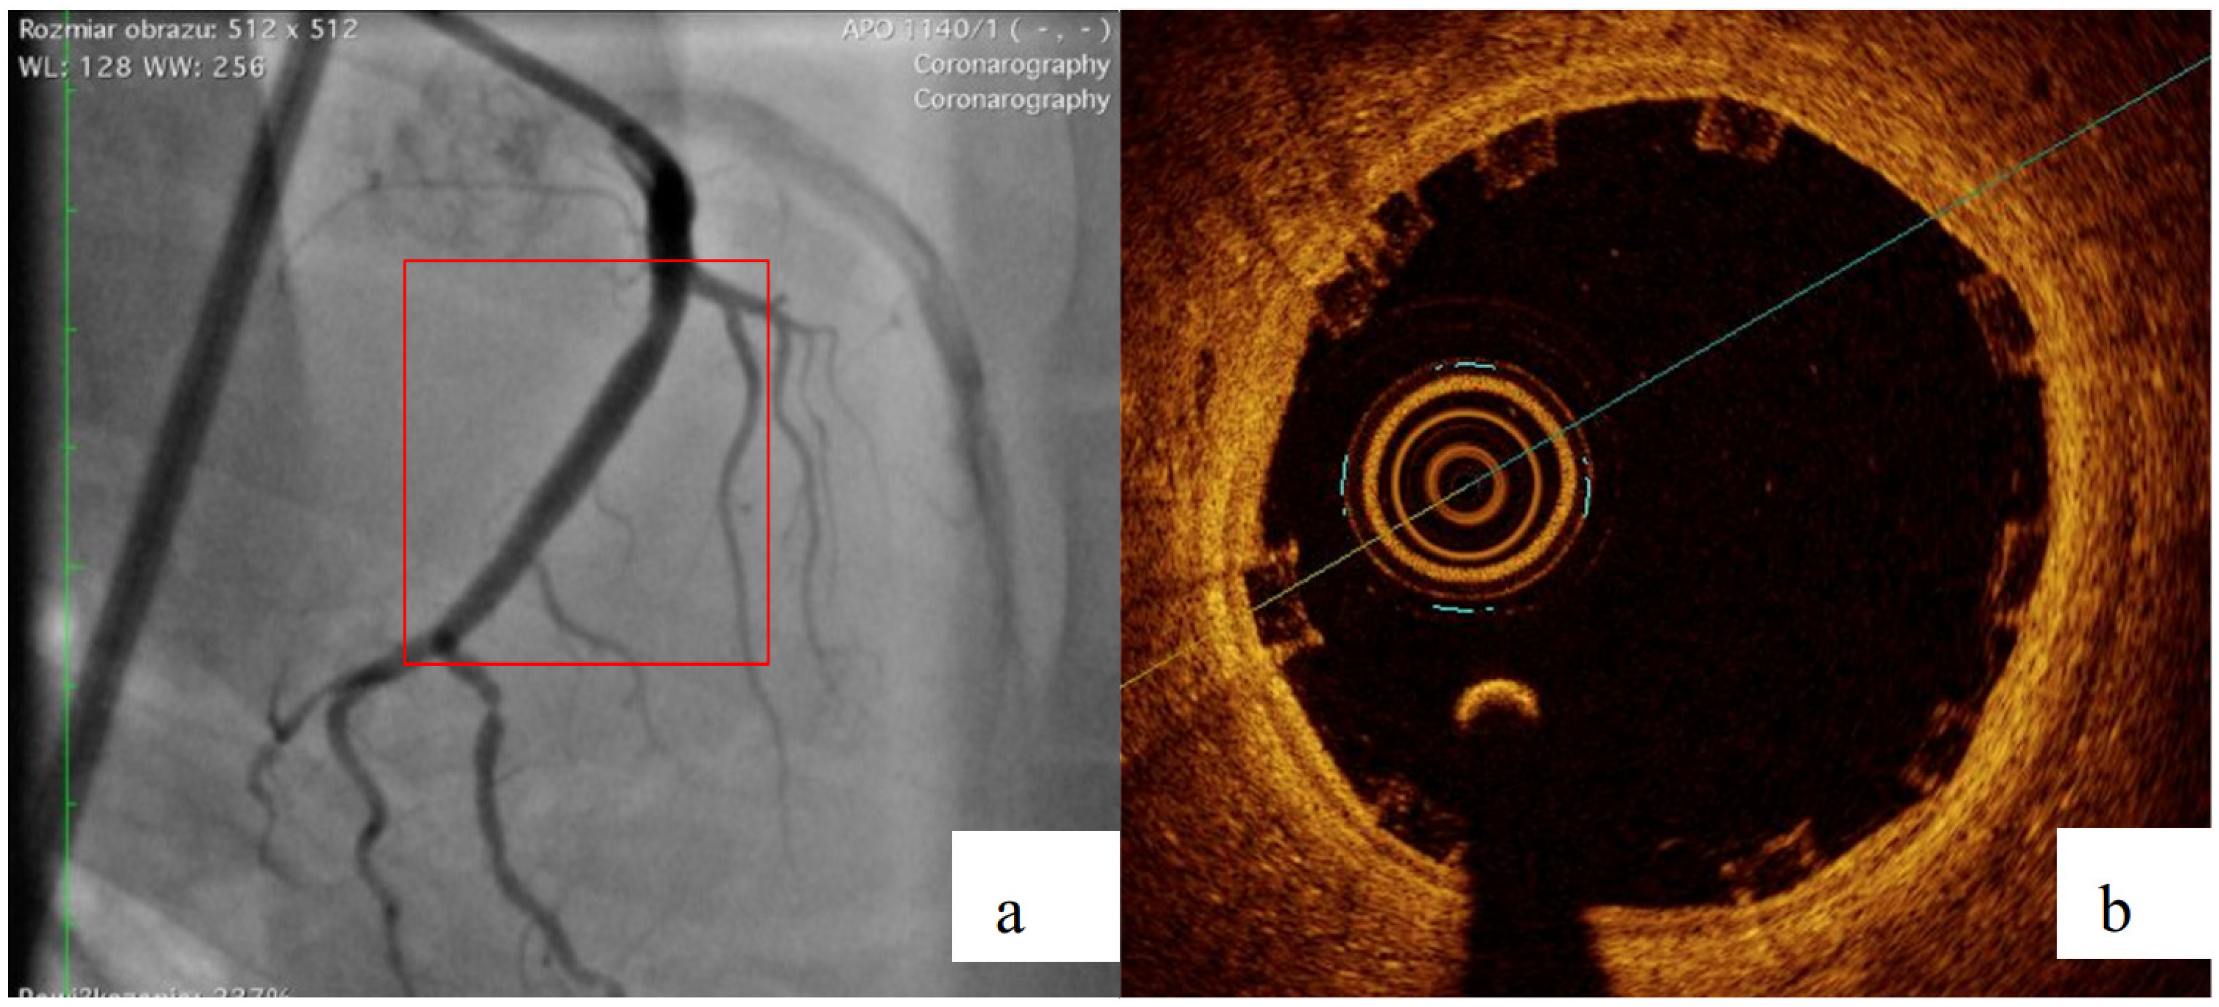

2.4. Biological Reponse in the Large Model of Coronary In-Stent Restenosis

The part of study was approved by local bioethical committee for animal experimentation (Medical University of Silesia, Katowice, Poland). To validate the mathematical and mechanical modeling tests described above, three PLGA/PLLA blend polymer stents (3.0 in diameter, 15.0 mm length) were implanted with standard percutaneous techniques in three coronary arteries of domestic swine with 110% overstretch. Following coronary angiography, intravascular optical coherence tomography (OCT) was utilized before and after the stent implantation to size the vessel. Stents were deployed after reaching body temperature with slow in mid portion of one of the three coronary arteries with stepwise inflation—2 atmospheres per 5 s. Following post implantation coronary angiography and OCT were performed. Animals were scheduled for 28-day follow-up with coronary angiography and OCT.

3.2. Biological Response

All three stents were implanted successfully. In coronary angiography stents showed enough radial force to support overstretched vessel (Figure 13). The OCT has shown good stent apposition and the analysis has shown lumen enlargement post implantation 24% as shown in Figure 13c. At 28-day follow-up, all stents were covered with neointima, and struts embedded. Interestingly the signs of material hydrolysis were observed thus proving the polymer amorphic properties (Figure 14).

Figure 13.

Acute outcome after PLGA/PLLA blend polymer stent implantation in coronary angiography (a) and optical coherence tomography (b). Lumen area increase before and after implantation (c). Geometrical view of vessel after stent implantation (d).